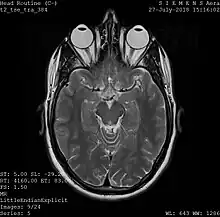

Magnetic resonance imaging

A magnetic resonance imaging instrument (MRI scanner), or "nuclear magnetic resonance (NMR) imaging" scanner as it was originally known, uses powerful magnets to polarize and excite hydrogen nuclei (i.e., single protons) of water molecules in human tissue, producing a detectable signal which is spatially encoded, resulting in images of the body.[5] The MRI machine emits a radio frequency (RF) pulse at the resonant frequency of the hydrogen atoms on water molecules. Radio frequency antennas ("RF coils") send the pulse to the area of the body to be examined. The RF pulse is absorbed by protons, causing their direction with respect to the primary magnetic field to change. When the RF pulse is turned off, the protons "relax" back to alignment with the primary magnet and emit radio-waves in the process. This radio-frequency emission from the hydrogen-atoms on water is what is detected and reconstructed into an image. The resonant frequency of a spinning magnetic dipole (of which protons are one example) is called the Larmor frequency and is determined by the strength of the main magnetic field and the chemical environment of the nuclei of interest. MRI uses three electromagnetic fields: a very strong (typically 1.5 to 3 teslas) static magnetic field to polarize the hydrogen nuclei, called the primary field; gradient fields that can be modified to vary in space and time (on the order of 1 kHz) for spatial encoding, often simply called gradients; and a spatially homogeneous radio-frequency (RF) field for manipulation of the hydrogen nuclei to produce measurable signals, collected through an RF antenna.

Like CT, MRI traditionally creates a two-dimensional image of a thin "slice" of the body and is therefore considered a tomographic imaging technique. Modern MRI instruments are capable of producing images in the form of 3D blocks, which may be considered a generalization of the single-slice, tomographic, concept. Unlike CT, MRI does not involve the use of ionizing radiation and is therefore not associated with the same health hazards. For example, because MRI has only been in use since the early 1980s, there are no known long-term effects of exposure to strong static fields (this is the subject of some debate; see 'Safety' in MRI) and therefore there is no limit to the number of scans to which an individual can be subjected, in contrast with X-ray and CT. However, there are well-identified health risks associated with tissue heating from exposure to the RF field and the presence of implanted devices in the body, such as pacemakers. These risks are strictly controlled as part of the design of the instrument and the scanning protocols used.

Because CT and MRI are sensitive to different tissue properties, the appearances of the images obtained with the two techniques differ markedly. In CT, X-rays must be blocked by some form of dense tissue to create an image, so the image quality when looking at soft tissues will be poor. In MRI, while any nucleus with a net nuclear spin can be used, the proton of the hydrogen atom remains the most widely used, especially in the clinical setting, because it is so ubiquitous and returns a large signal. This nucleus, present in water molecules, allows the excellent soft-tissue contrast achievable with MRI.[6]